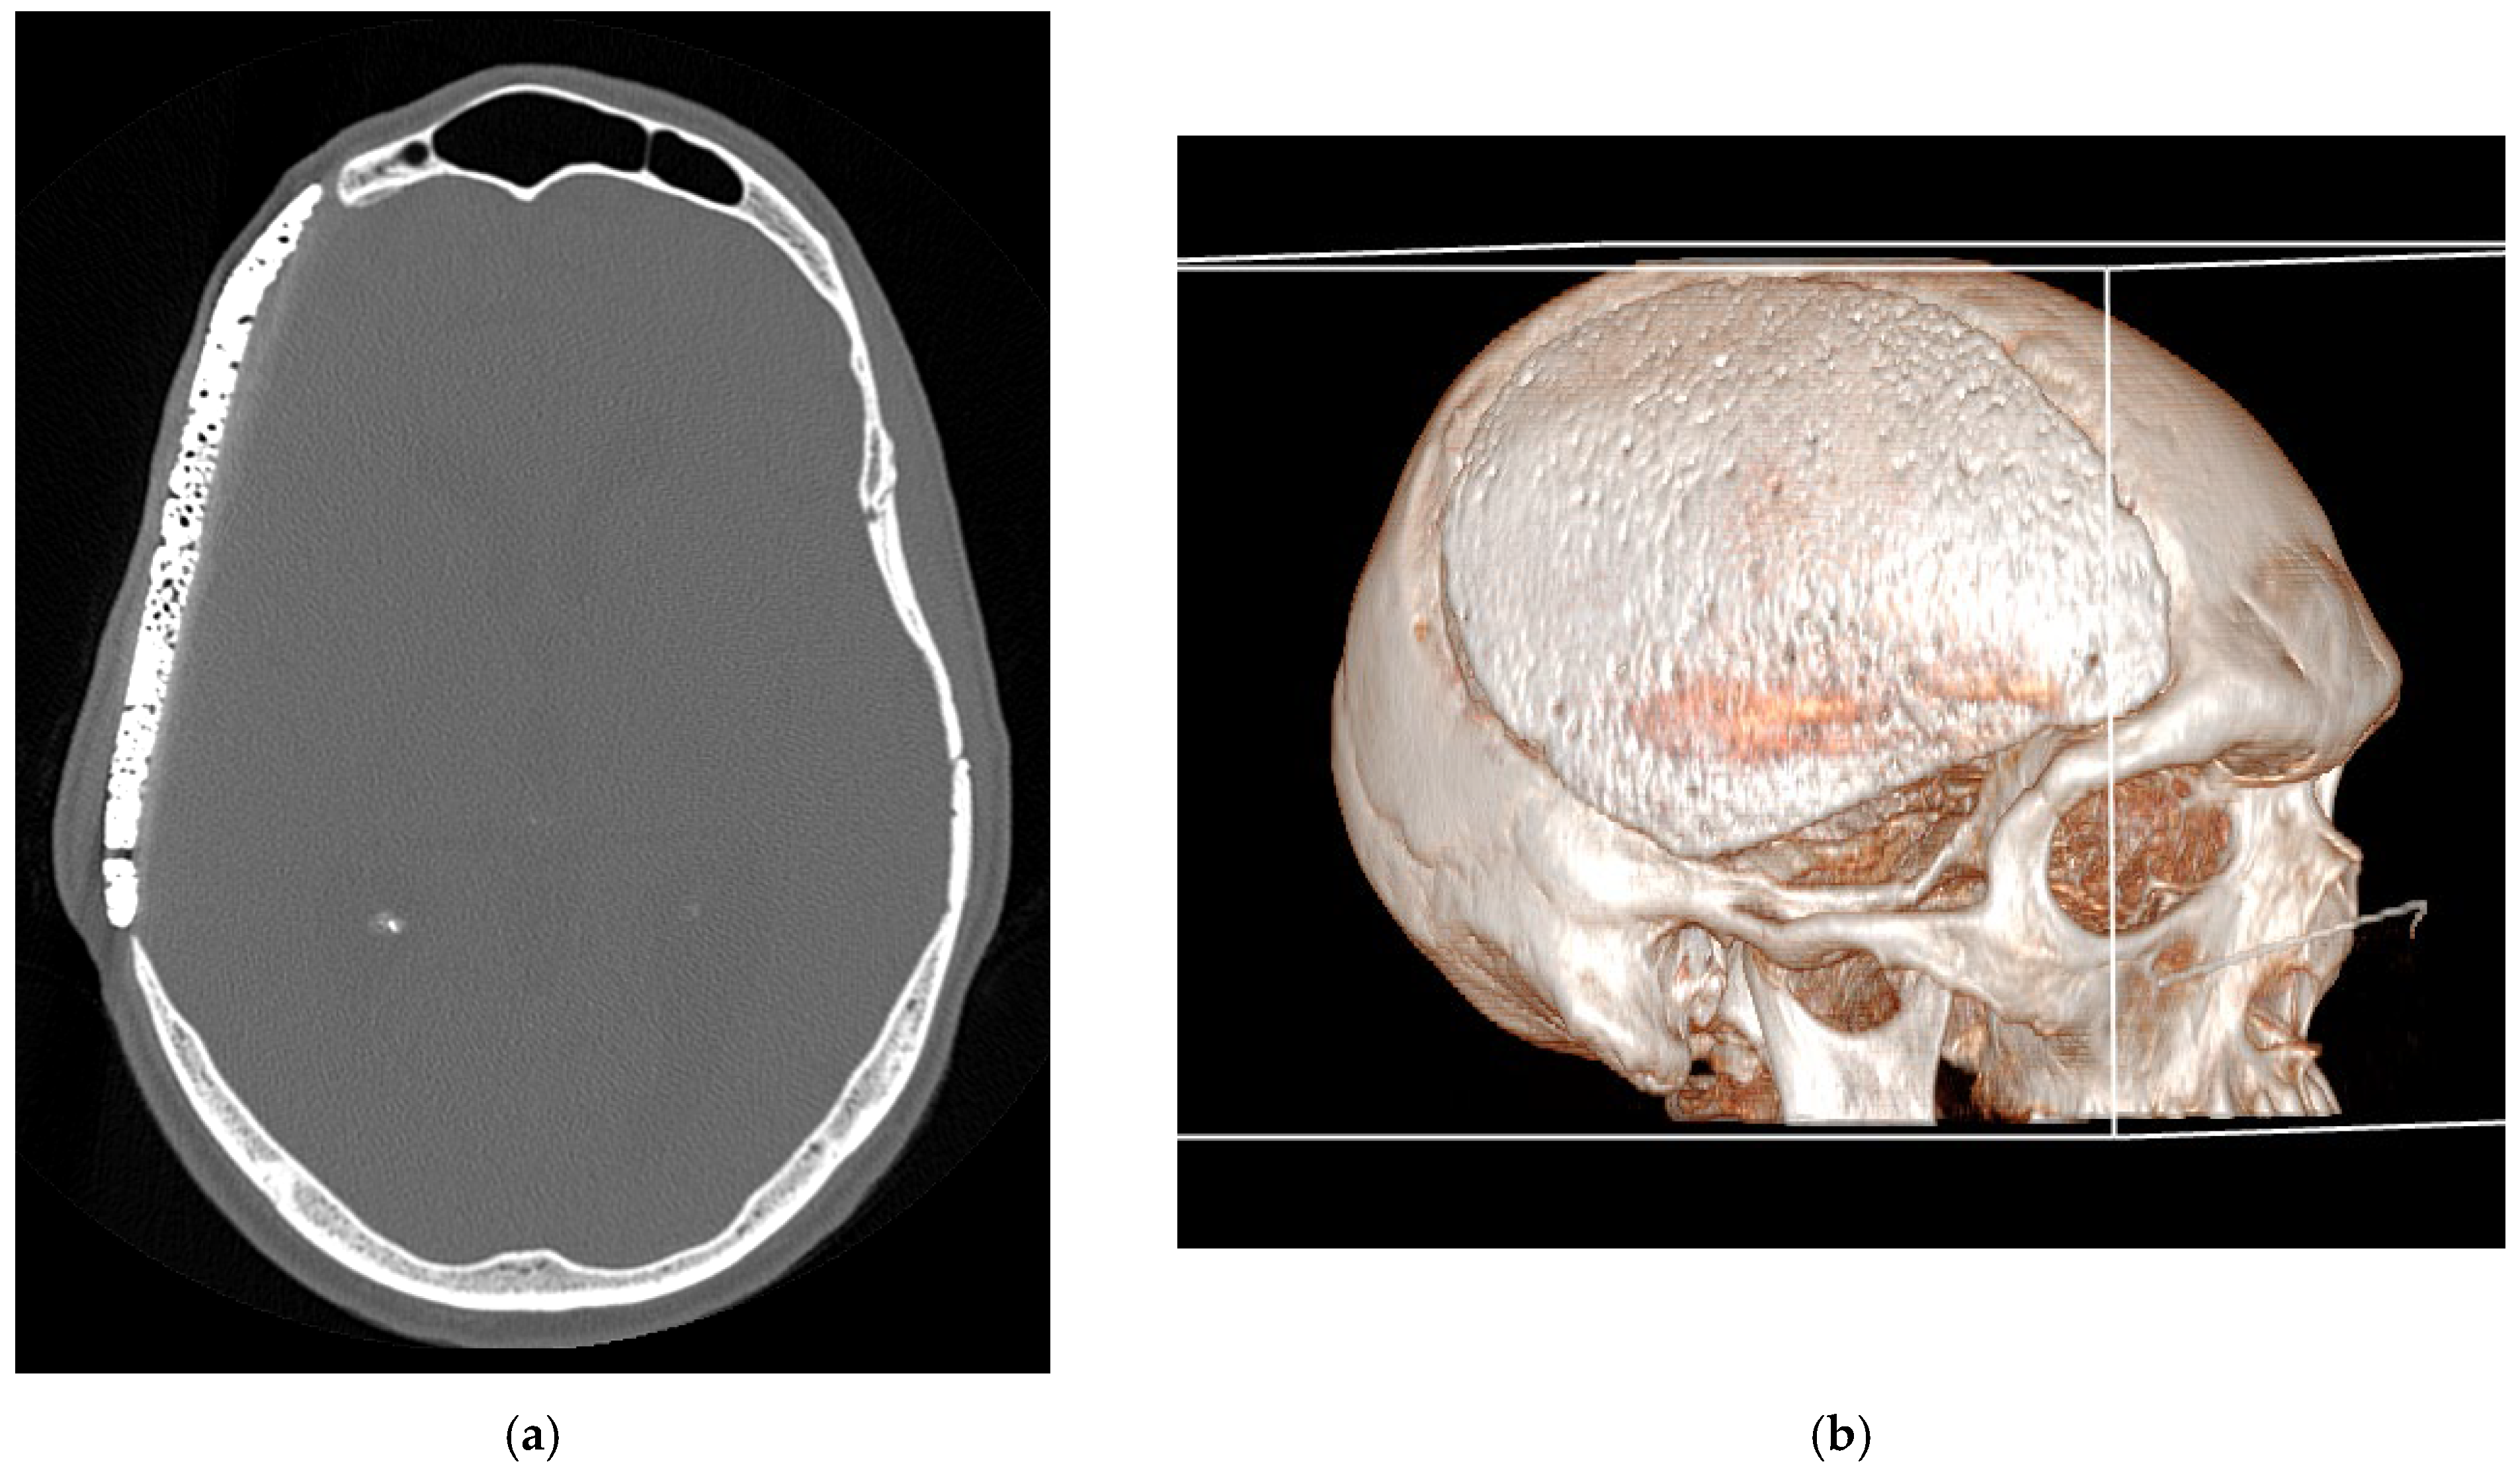

Radiological assessments, while performed, demonstrated progressive osseointegration, with bone remodeling visible at the prosthesis margins (Figure 5).

Figure 5. Progressive osseointegration with bone remodeling visible at the prosthesis margins.

Long-term clinical follow-up (mean duration: 42 months) revealed no cases of secondary displacement, prosthesis fracture, or foreign body reaction. The PHA implants maintained their structural integrity, and no patient required revision surgery. Cosmetic outcomes were rated as excellent by all patients, with restoration of normal cranial contour and no palpable irregularities at the surgical site.